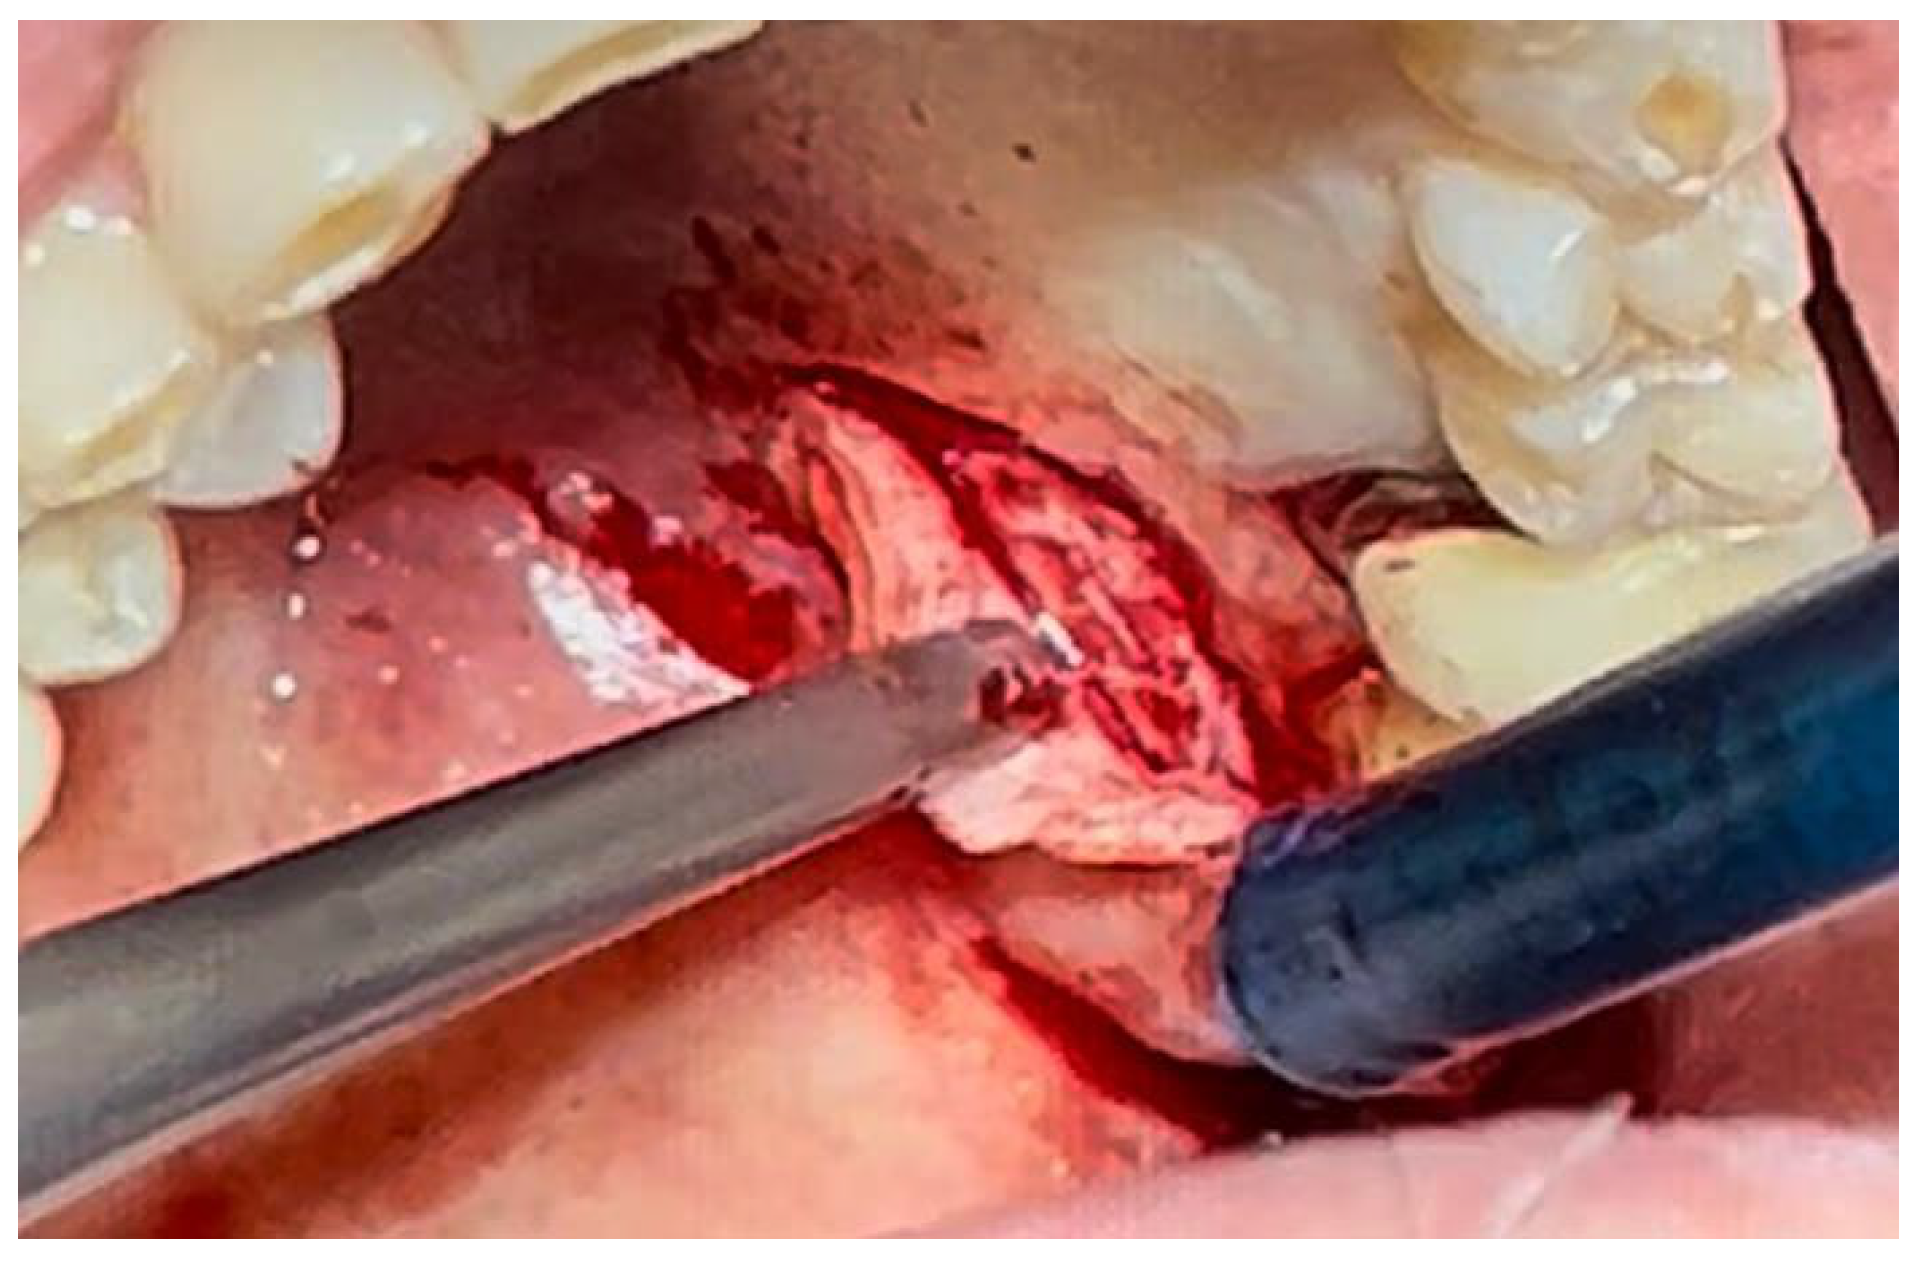

A similar technique was used in a 45-year-old patient with controlled hypertension, treated for the extraction of tooth 1.6 (Figure 11) and subsequent post-extraction implant-prosthetic rehabilitation (Figure 12). The surgical site was treated with bone graft material (Bio-Oss®—Geistlich), and a small amount of Glubran II was applied (Figure 13). Once again, Glubran II proved to be highly effective in stabilizing the graft material at the surgical site, providing excellent hemostasis and strong mechanical resistance from the film formed after polymerization (Figure 14).

Figure 10. Surgical site at the end of the polymerization time of Glubran II; the site was subjected to tensile testing, with positive results under the applied tensions.